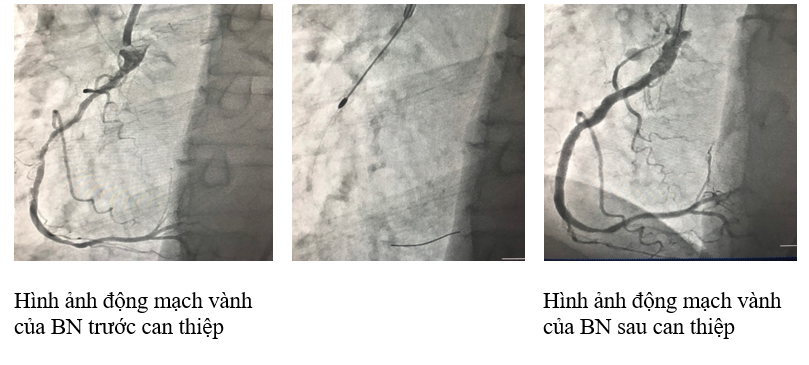

Sau khi hội chẩn các chuyên khoa liên quan, Ê kip các Bác sĩ của Đơn vị Can thiệp tim mạch Bệnh viện Đa khoa tỉnh Thanh Hóa cùng với sự hỗ trợ của chuyên gia tuyến trên đã quyết định áp dụng kỹ thuật Rotablator (khoan cắt mảng xơ vữa), sử dụng mũi khoan nhỏ 1,25-1,5-1,75 mm gắn kim cương rất nhỏ, được đưa vào tổn thương động mạch vành qua một dây dẫn nhỏ và được điều khiển quay với vận tốc rất cao để khoan thủng các tổn thương hẹp do mảng vữa vôi hóa…Từ đó dễ dàng tiến hành nong và đặt 02 stent cho bệnh nhân. Ngay sau can thiệp bệnh nhân đỡ đau ngực, đỡ khó thở. Sau 6 ngày điều trị bệnh nhân đã ổn định, đủ điều kiện xuất viện…